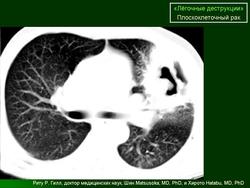

ОГК. Легочные деструкции (кавитации). +

Легочные деструкции (кавитации)

Легочные кавитации. Радиопедия.

Случай 7: SCC